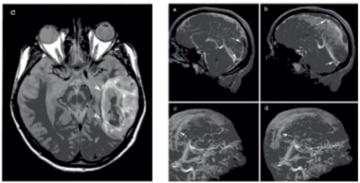

• evidenţiază absenţa fluxului sau lipsa opacifierii în achiziţiile 3D FSPGR postGd la nivelul sinusului trombozat (Fig.2).